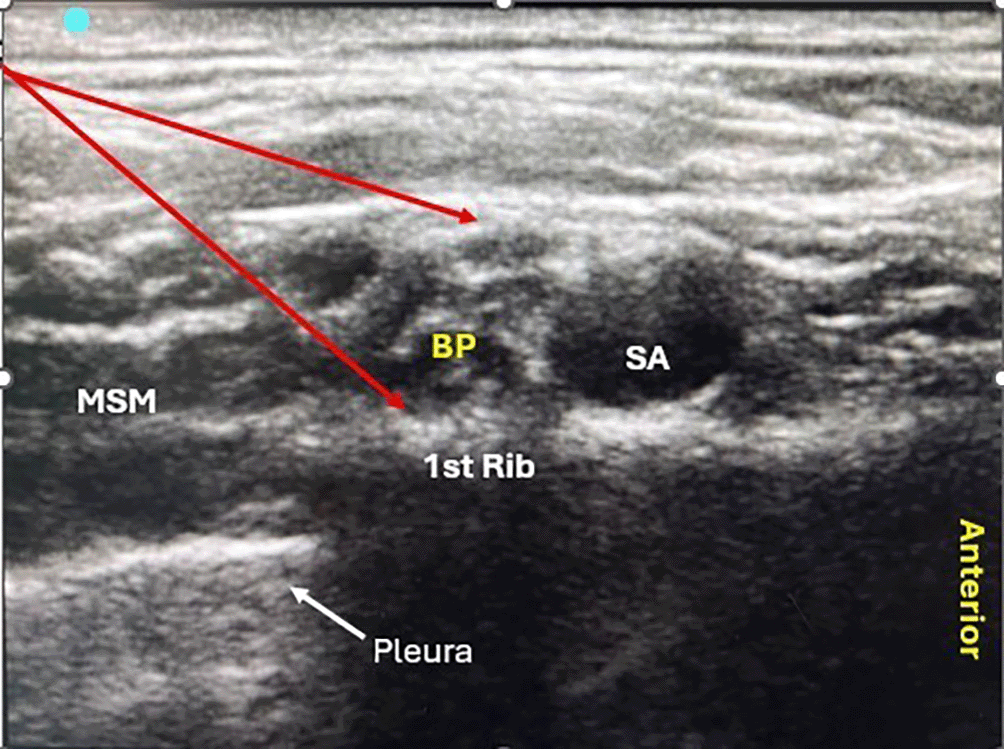

Supraclavicular brachial plexus block (SCBB) has emerged as a popular technique, largely due to its superior blockade quality, rapid onset, and dense blockade.2 The introduction of ultrasound guidance has significantly enhanced the accuracy and safety of the procedure, aiding in the visualization of normal and abnormal anatomical variations and the spread of local anesthetics. This technological advancement has notably improved the quality and success rate of the block, providing anesthesiologists with a powerful tool for patient care.3

Pre-anesthetic evaluation was performed the day before surgery. On the day of surgery, the NPO status was confirmed. The patients baseline heart rate, blood pressure, and oxygen saturation were recorded. An intravenous cannula was then secured to the unaffected limb. The block was performed in a supine position with a 45° head-up position, and the patient’s head was turned towards the unaffected side. Under sterile aseptic precautions, the consultant anesthesiologist administered the ultrasound-guided supraclavicular block via an in-plane technique (IP) ( Figure 1). After administration of the block, the onset and duration of sensorimotor blockade and sedation score were recorded.